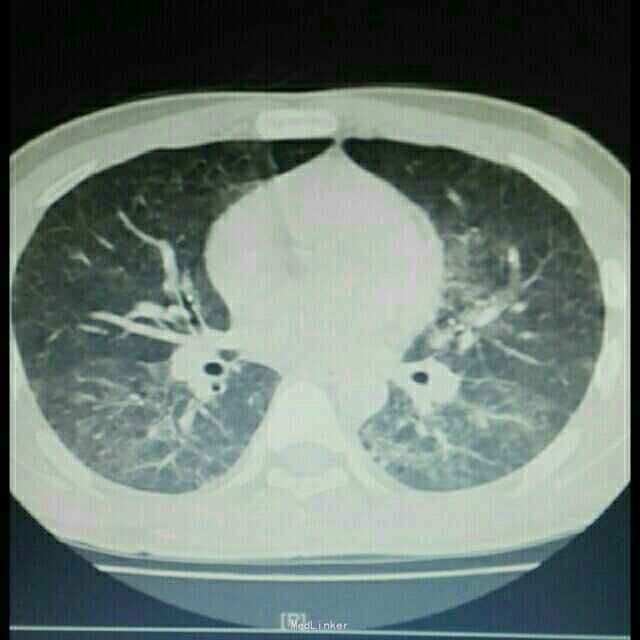

肺部感染严重吗

肺部感染严重吗,肺部感染真实

梅迟外婆,陈荣菊,肺部感染严重,高度疑似新型肺炎.

患者肺部感染情况,后来逐渐康复.

又一例严重的肺部感染

肺部感染ct图片

肺部感染ct

严重肺部感染ct图片

肺部感染的ct影像图片